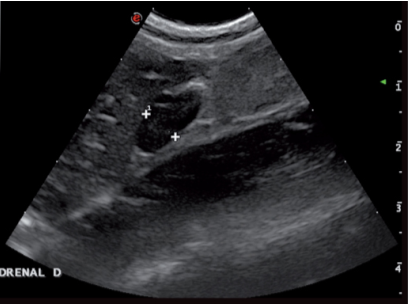

肾上腺肿瘤的超声表象包括肿块,钙化和异常回声(图4)。需要注意的是,增大的肾上腺或肾上腺肿块并不意味着它会分泌过多的醛固酮。这些肾上腺上的肿瘤但不引起临床症状的称为偶发瘤。功能性肿瘤会分泌如皮质醇,孕激素等激素,嗜铬细胞瘤也属于功能性肿瘤。

最近的一项研究将肾上腺肿块回声分成三种模式:不均匀的高回声,均匀的低回声和中心高回声外周低回声(靶征)。研究试图仅通过回声模式去区分肿瘤的良性恶性,不去评价血管浸润,对侧肾上腺的大小,形状及回声情况。结果表明,仅以超声模式去区分肿瘤的良性恶性是不可行的。有两例通过超声检查发现一侧肾上腺肿块的病例中,尸检时却发现它实际患有双侧肾上腺癌。所以作者认为双侧肾上腺肿瘤的真实患病率可能有被低估。在其他尸检确诊双侧肾上腺增生的病例中,却没有发现超声变化。说明正常超声表现的肾上腺也不能排除良性或恶性肿瘤浸润的可能性。

垂体依赖性肾上腺皮质功能亢进易发生于中老年的猫。80%的病例会伴发糖尿病。超声可见双侧肾上腺增大(垂体依赖性肾上腺皮质功能亢进)或肾上腺上存在肿块。单侧肾上腺肿瘤产生过多的皮质醇,会导致对侧肾上腺萎缩。